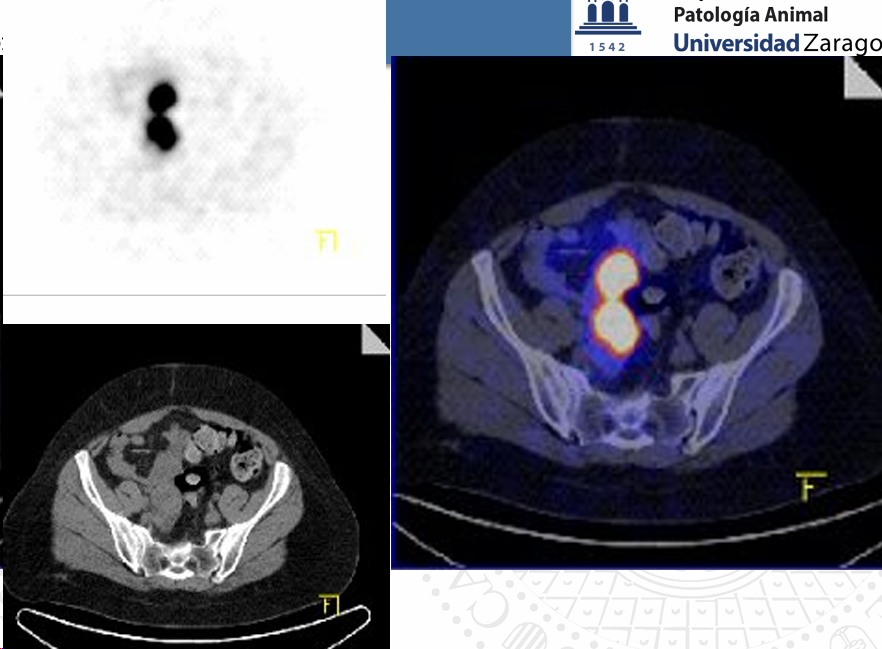

**PET TC o Tomografía por Emisión de Positrones – Tomografía Computarizada

- PET: Tomografia por emision de positrones

- Se inyecta un radionúclido generador de positrones 18F

- Se necesita un ciclotrón cercano

- El 18F se une a la glucosa 18FDG (trazador)

- Valoramos la via glicolítica de la glucosa Las células tumorales tienen un metabolismo muy incrementado Captan la glucosa marcada

- Unidades SUV (standard uptake value). Si son > 2.5 ó 3 = NEOPLASIA

Hay diferentes tipos de PET y crean imagenes de fusion danto tanto imagen anatomica como funcional al mezclarla IMPORTANTE